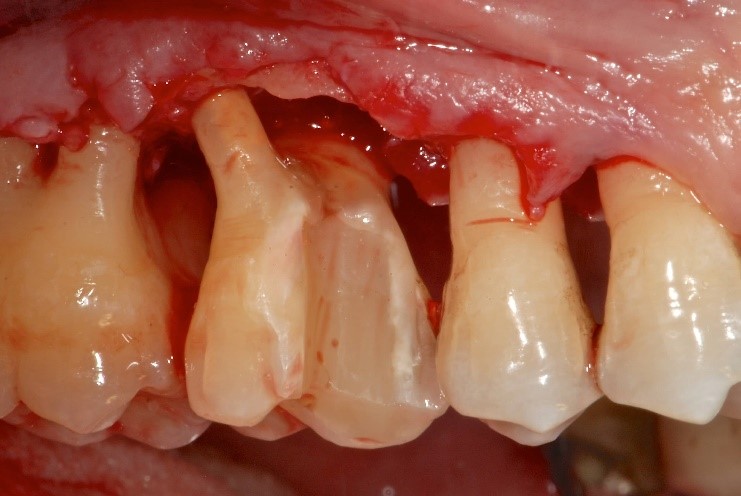

The pockets will act as a receptacle for subgingival tartar and bacteria. In the strenuous fight between bacterial toxins and immune defenses, the one who loses out is the alveolar bone, which will progressively reabsorb upwards until the tooth is left exposed. As a result, the tooth without surrounding bone will begin to loosen until it falls out , in the absence of appropriate diagnosis and treatment.

The diagnosis of periodontal disease (pyorrhoea) is made very simply and non-invasively using a millimeter instrument, the periodontal probe , which is slid between the surface of the root and the gum and allows the presence of notches to be assessed and to be measured. the severity of the injury.

Following the first local therapy sessions, which as mentioned consist of oral hygiene instructions, removal of tartar above and below the gums and superficial portions of the root (cement) if infected, the patient is re-evaluated for any secondary needs. This first therapeutic phase, which may represent all that is necessary to do, is carried out by the dentist or dental hygienist

In cases where this first therapeutic phase does not correspond to the elimination of the pockets or the complete resolution of the tissue problems, in the more serious and more advanced cases the therapy becomes the responsibility of the dentist who mainly deals with periodontology. If not managed or, worse, underestimated and not treated in time, periodontal disease evolves into pyorrhea , the final phase in which tooth loss inexorably and progressively occurs, with consequent reabsorption of the alveolar bone (i.e. the bone that keeps the teeth in place). function).